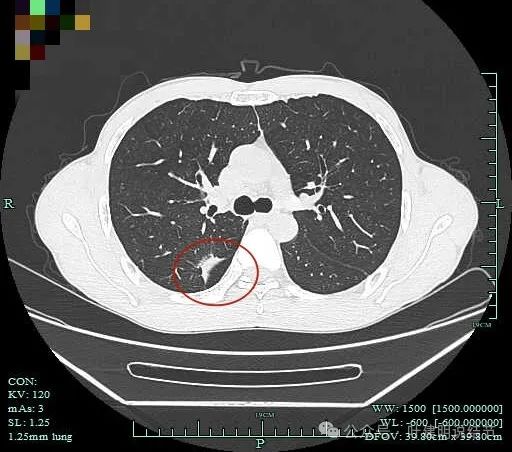

既往对比:

上图是2023年1月时的,虽也基本上实性,但明显病灶相对较小,而且膨胀感不太明显些。

病灶1于2023年9月时都没有的,更说明是炎症性的。